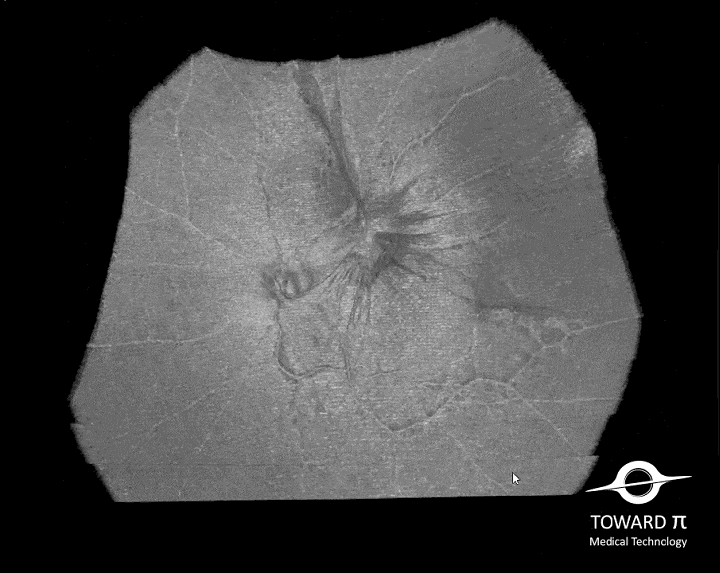

BMizar (BM-400K) es el OCT más potente de la industria con una fuente de barrido de 400 kHz. Su excepcional diseño óptico eleva la experiencia de la Angiografía OCT a un nivel sin precedentes. Con imágenes de alta definición de la retina, la coroides y el segmento anterior, cubre sin esfuerzo un área increíblemente grande en un solo escaneo (logrando un OCTA de 24 mm de ancho en solo 7-15 segundos).

Galería OCTs del TowardPi BMizar